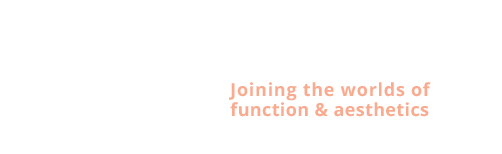

Kaakchirurgie

- Vertikale verkorting bovenkaak (Le Fort I)

- Implantaten met osteotomie